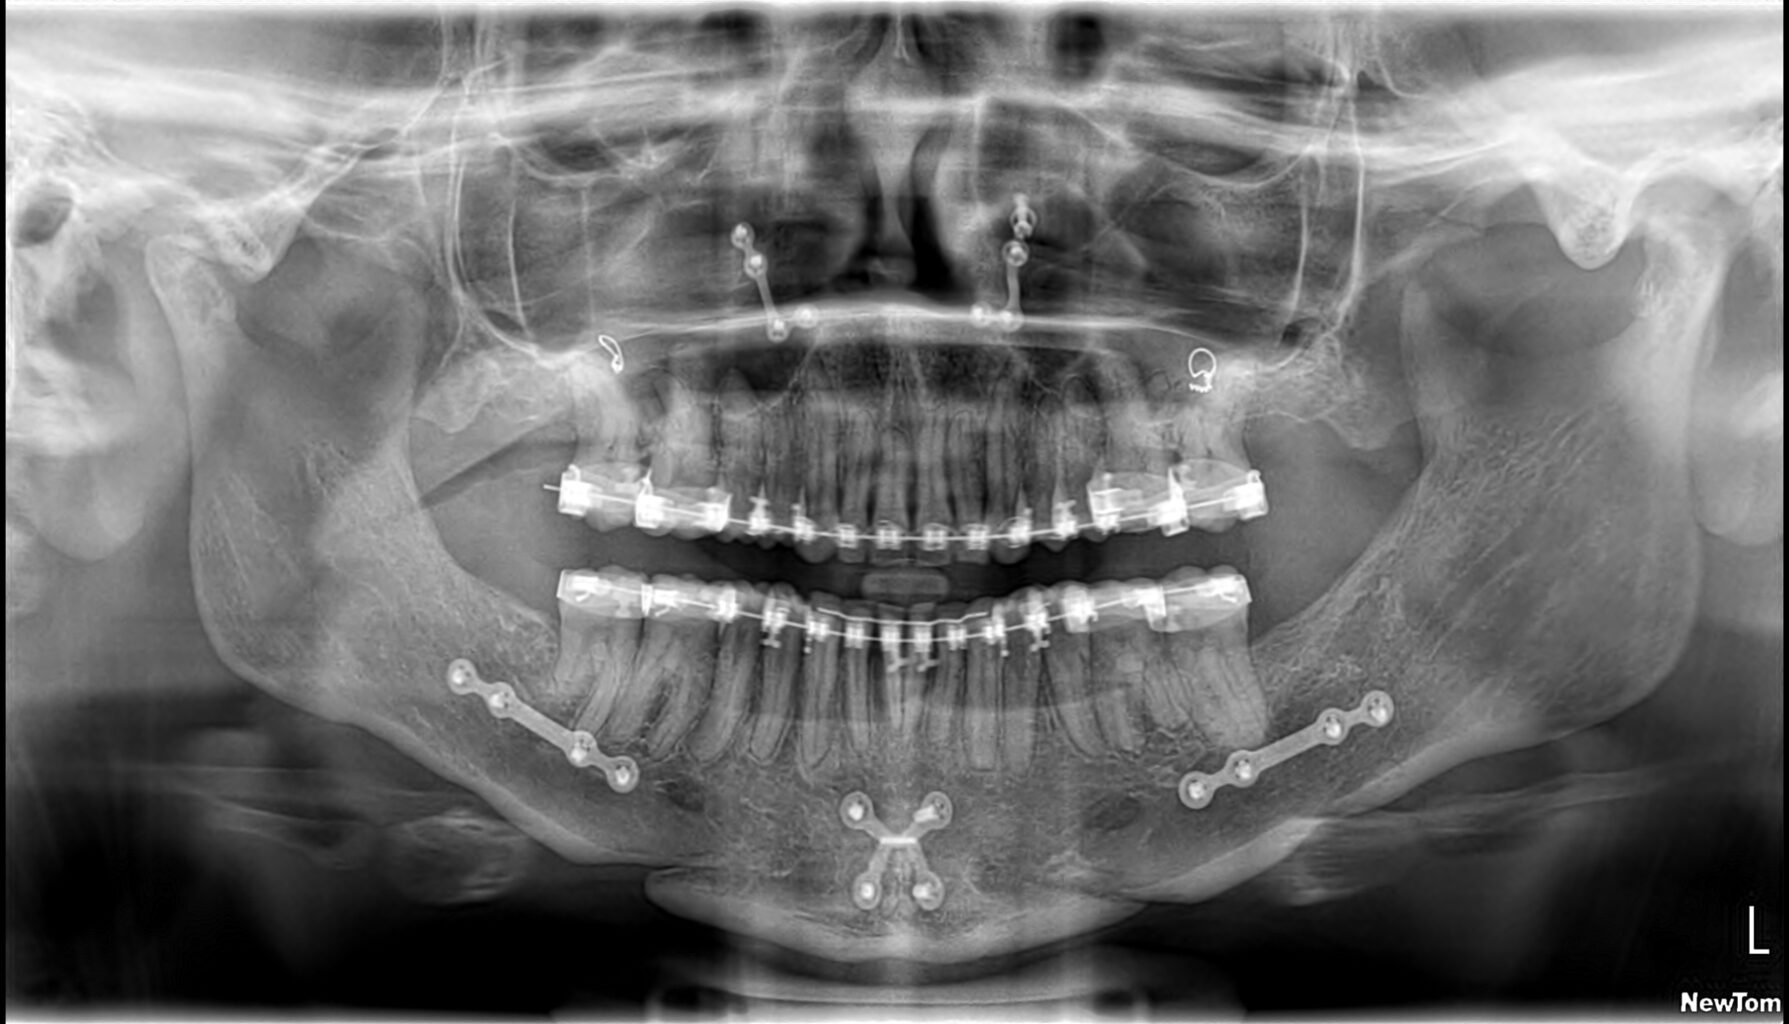

Als de orthodontische voorbereiding voor de operatie ver gevorderd is, wordt de kaakoperatie door de kaakchirurgen digitaal gepland in 3D.

Met een prachtig digitaal planningsprogramma in samenwerking met het UMCG, wordt bepaald wat het mooiste resultaat geeft. Hieronder geven we voorbeelden van hoe zo’n planning er uit kan zien. In dit voorbeeld wordt de bovenkaak verplaatst, de onderkaak en de kin. Vaak kan de operatie ook beperkt worden tot alleen een onderkaak of alleen een bovenkaak. Het is maar net wat per specifiek geval de beste oplossing is.

en het effect daarvan op de ‘weke delen’ zoals lippen en kin en profiel.

Nu kan dee kaakchirurg goed voorbereid de operatie plannen.